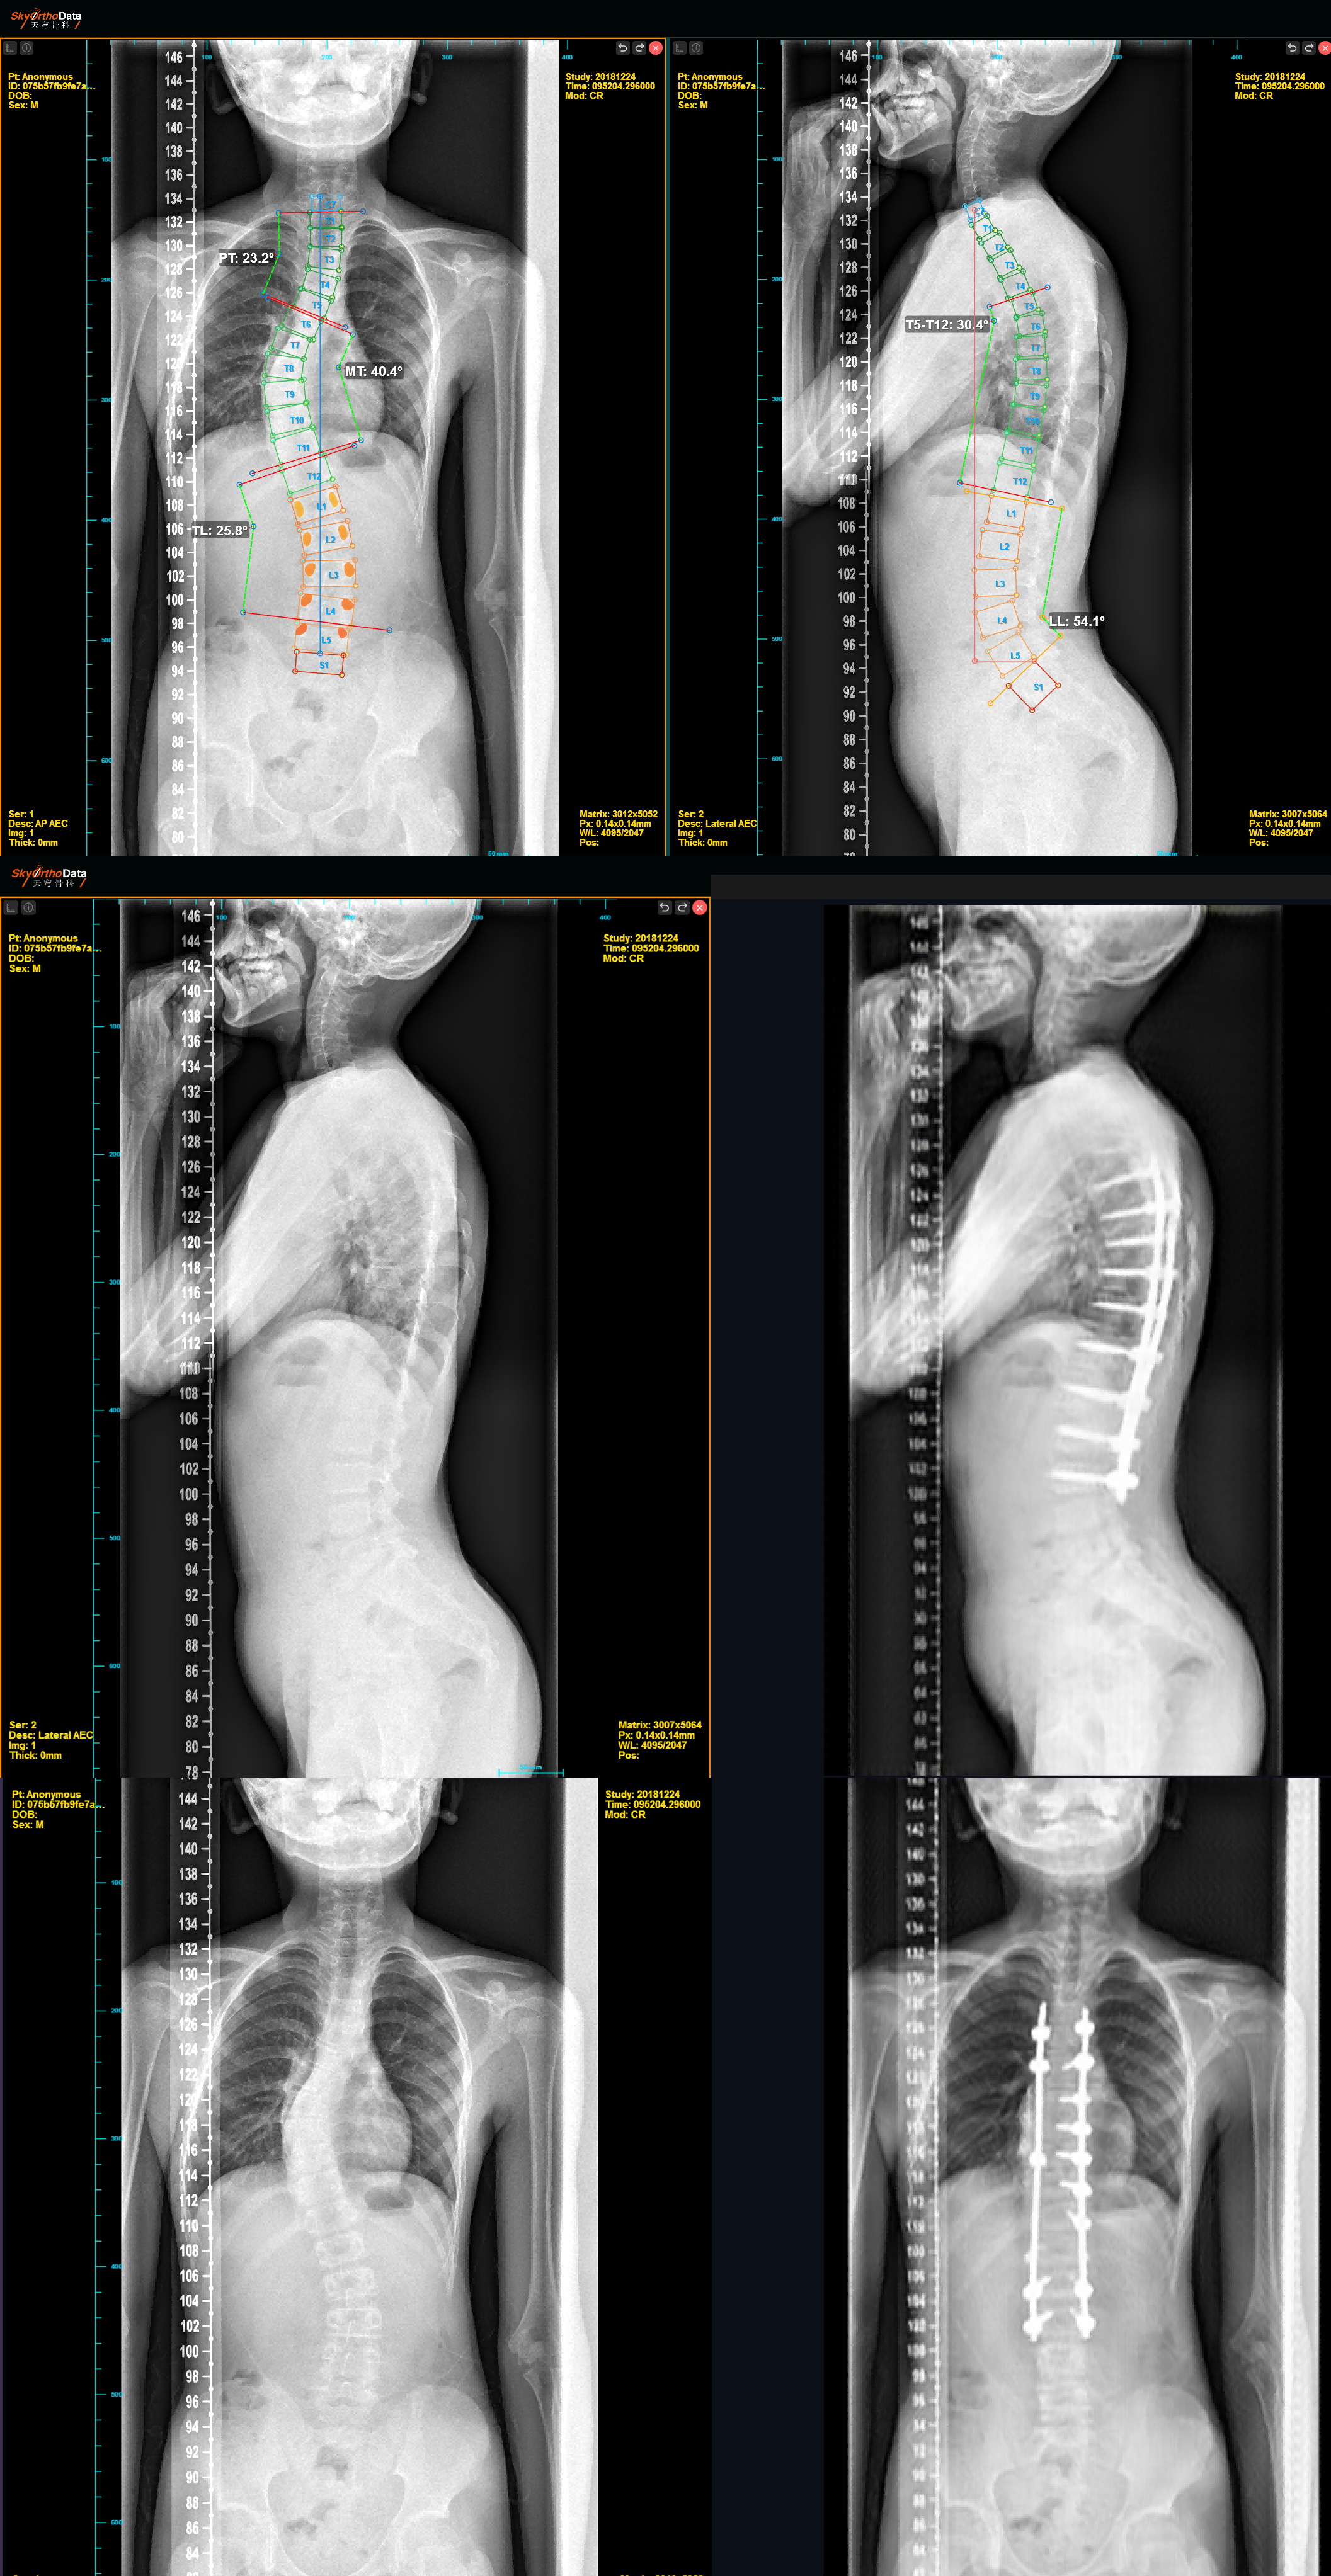

子课题四《脊柱畸形智能影像评估及术前规划新产品研发》中,德康医疗共同开发的“基于深度学习模型的脊柱畸形多维度高清成像评估系统”,目前已完成基于深度学习的自动椎体识别、自动测量和分型判定的一整套全流程2D手术规划系统,并已在较大规模数据集上完成了CT分割椎体任务,实现了高精度3D椎体分割和分类识别。

子课题五《脊柱畸形新型矫形和椎间融合系统的研发》中,德康医疗研发的钴铬钼胸腰后路内固定系统和插片式自稳定型腰椎融合器已完成申请国内发明专利7项,国际发明专利2项,产品在多家医院的多中心临床研究中完成临床应用。

子课题六《新产品和系统的前瞻性、多中心临床评价及验证》针对脊柱畸形筛查系统、智能诊断、预后系统、矫形内固定系统、椎间融合系统开展临床多中心队列研究。自2025年3月启动入组工作以来,在子课题六牵头单位中国人民解放军总医院的推动下,项目各成员单位有序推进新型矫形内固定系统和插椎间融合系统病例入组,近期将启动脊柱畸形筛查系统、预后模型及智能诊断系统的多中心队列研究。